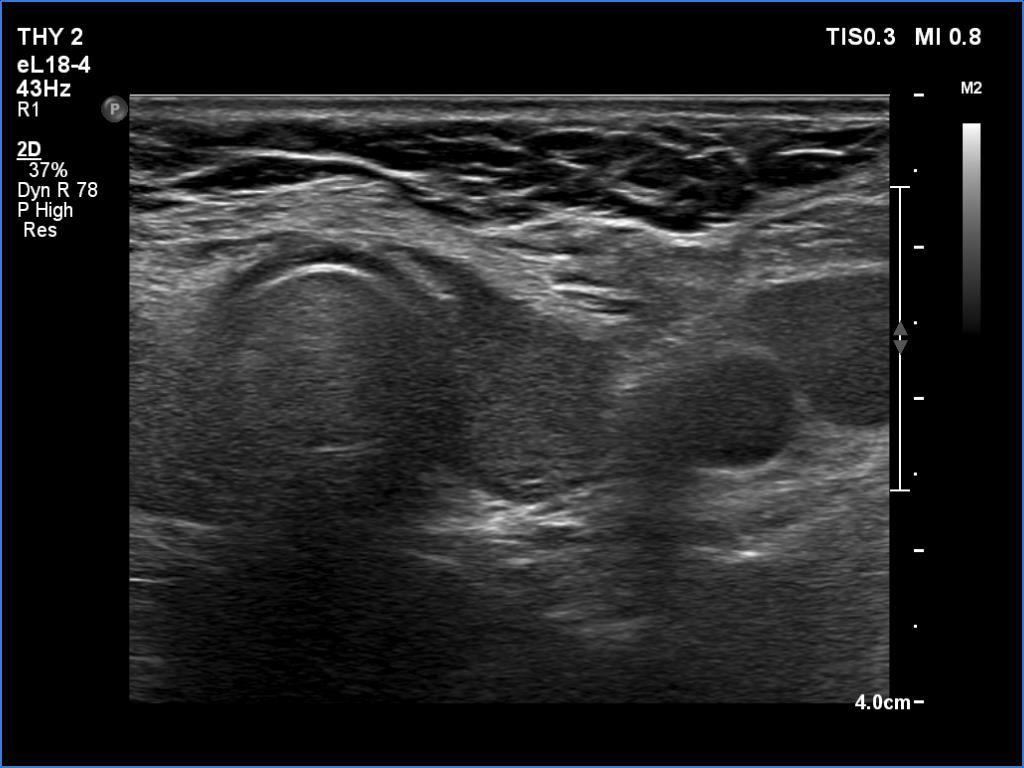

Lymphocytic thyroiditis - case 751

Right lobe

Left lobe

Focal form of lymphocytic thyroiditis is presented. The thyroid has numerous discrete, hypoechoic lesions which correspond to more active foci of thyroiditis. The interpretation of this pattern should not cause concern - these areas are not pathological nodules. The discrete lesions have non-regular, partly clearly lobulated or spiculated margins.